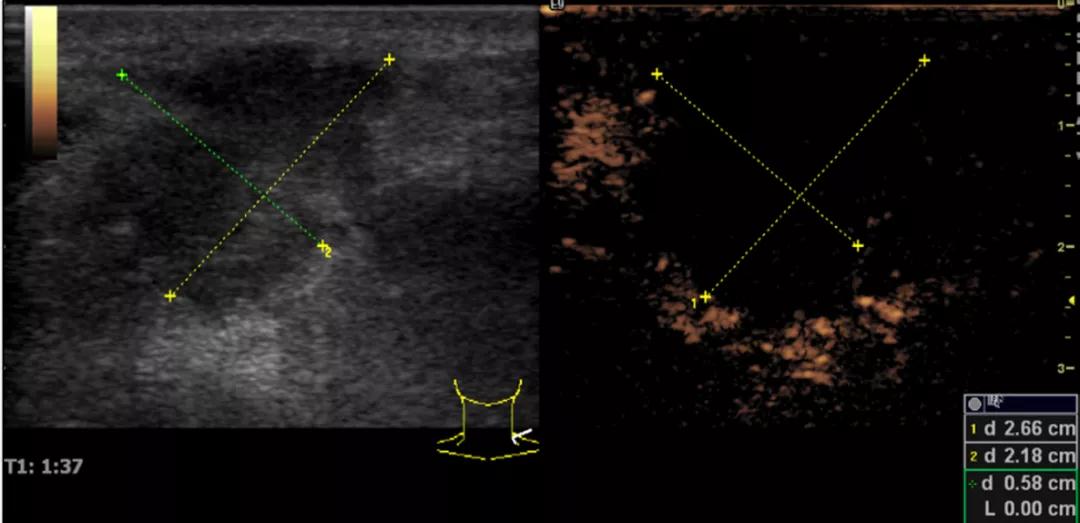

随后,徐栋教授进一步分享了五个临床实战病例,带来了更直观的热消融治疗经验。第一个病例是62岁肺癌患者,术后1年余发现双侧锁骨上淋巴结复发,侵犯神经,存在静脉回流、淋巴回流障碍,肿胀、疼痛非常明显。影像显示患者淋巴结边界不清、形态不规则,存在浸润,血流强化增强。由于患者在系统治疗后进展,且主要目的缓解症状、减瘤。局麻下行热消融术,从后向前逐层消融,热消融之后超声造影即刻评估显示完全充盈缺损,完全覆盖病灶。

(病例1图例)